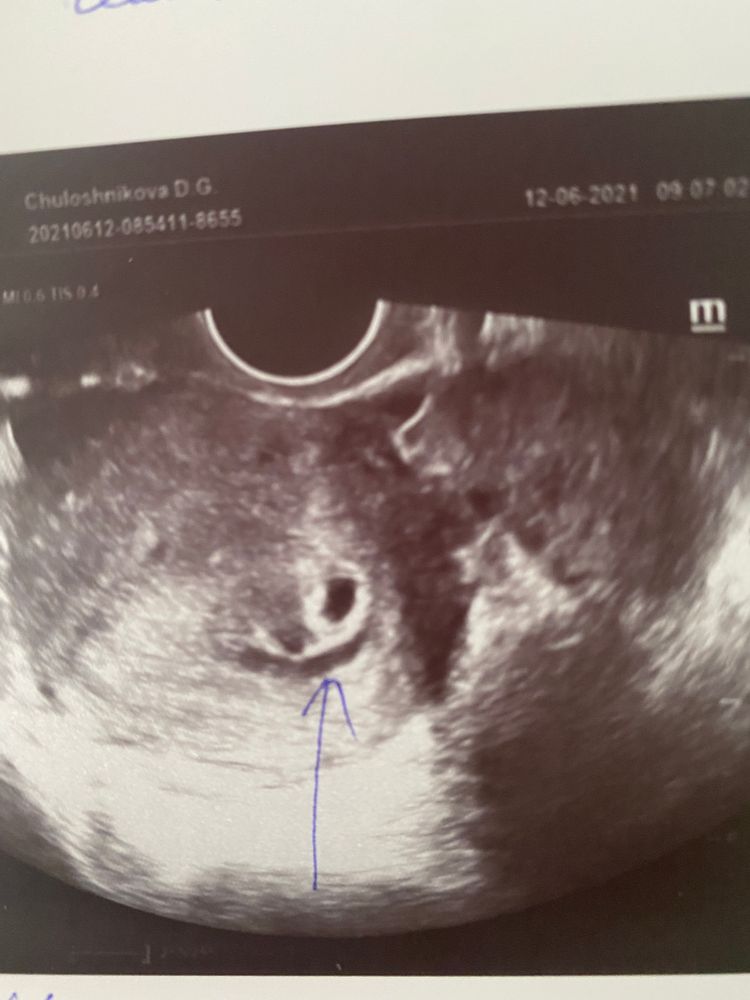

Узи 4 дня задержки

Узи 4 дня задержки 147 фото